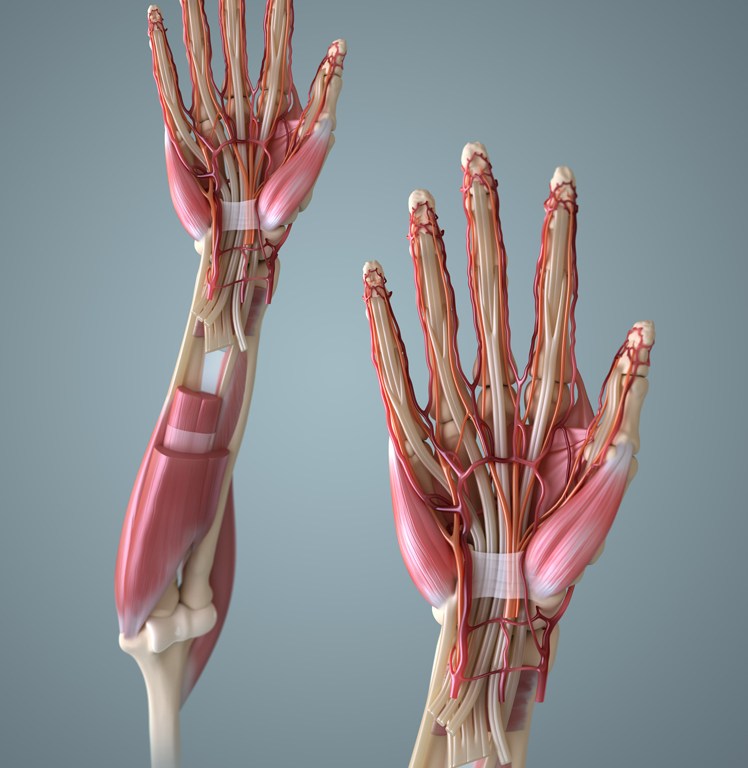

Strength: The hand has what seems like a thousand muscles & tendons. While there’s actually only 34, that’s pretty impressive for such a small area. What not to do: push, pull and hand shank the guy until eventually they say ouch. While I’m clearly being ridiculous, that’s pretty much what I was doing until I was shown a better method. What to do: Have your patient perform 3 simple hand gestures to appreciate any weakness. OK (median n.), thumbs up (radial n.) and fingers crossed (ulnar n.).

Tendons: If there’s possibility of a tendon rupture or you simply want to check to confirm that the flexor tendons are intact, have you patient make a claw and resist you while you attempt to pull each one of the fingers away. Laxity indicates a deficit in either strength or the tendon itself and should be noted.